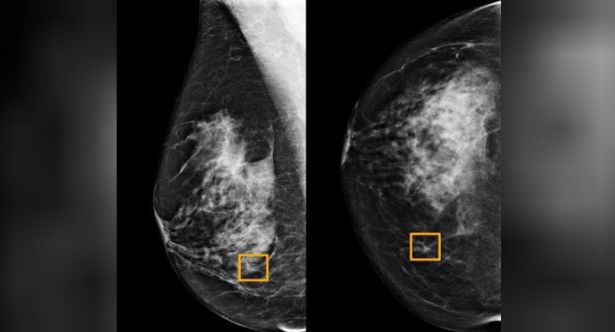

W trakcie testów sztuczna inteligencja dokonała analiz ponad 28,5 tys. mammogramów w Wielkiej Brytanii oraz z górą 3 tys. takich badań w Stanach Zjednoczonych.

Okazało się, że w USA AI zredukowała o 5,7 proc. przypadki, w których lekarze fałszywie zdiagnozowali raka piersi u pacjentek, u których w rzeczywistości ta choroba nie wystąpiła. Z kolei o 9,4 proc. zmalała liczba przypadków, w których kobiety uznane przez lekarzy za zdrowe w rzeczywistości chorowały na nowotwór piersi.

W Wielkiej Brytanii testy wykazały zmniejszenie liczby fałszywych dodatnich wyników o 1,2 proc., zaś fałszywie negatywnych – o 2,7 proc. Dysproporcje w wynikach osiągniętych w USA i Wielkiej Brytanii mają wynikać z tego, że w tym drugim kraju analizy testów mammograficznych dokonywane przez lekarzy są systemowo bardziej precyzyjne niż w Stanach.